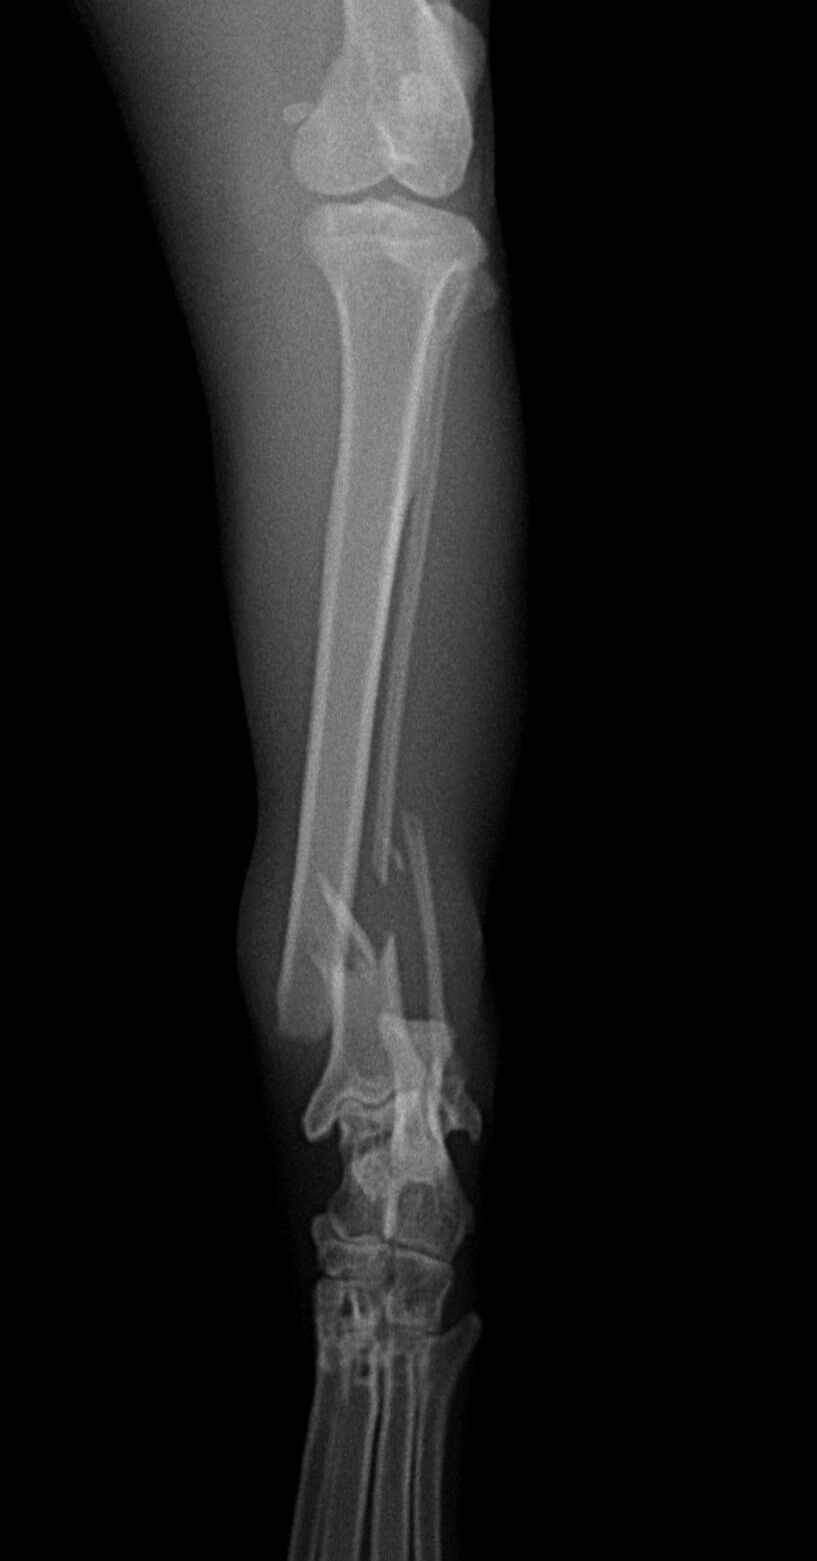

脛骨 腓骨の骨折 動物病院 京都 京都市内北区 上京区 右京区他 年中無休 夜間救急

ネコちゃんの脛骨骨折の治療 症例報告 動物病院をお探しの方にお役立てになれる最新情報を発信 大阪市の動物病院はフジタコーポレーション株式会社

脛骨骨折 骨折 整形外科 診療科目 エルムス動物医療センター